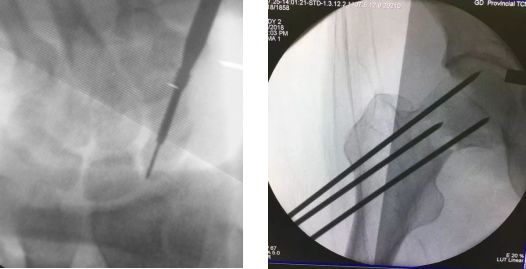

1、克氏针导向作用

将克氏针紧贴于骨表面插入,可以为后续的钻孔、置入螺钉提供导向作用,提高成功率,常用于骨盆、股骨颈、股骨髁等位置。

但是,目前创伤骨科手术中克氏针的最大用途还是骨折复位后以及接骨板的临时固定。

有时候,克氏针临时固定后也可做为导针使用便于置入其它内固定物,如空心螺钉、Herbert螺钉等。

术中还可当做复位器对骨折进行撬拨复位。同时还可做为肢体力线的一种参考标志,指导术中内植物的置入和截骨矫形。